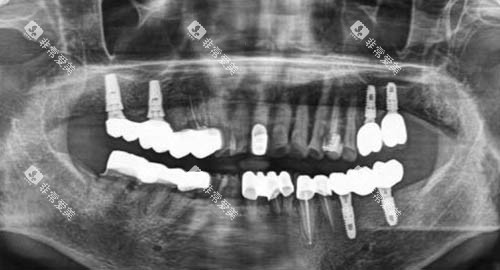

同时,门诊部设施齐全,配备了较高的医疗设备,如全景X光机、智能化口腔扫描仪等。

这些设备的引入,进一步提升了诊疗的确切度和效率,让患者能够得到更比较准的诊断和治疗。

该门诊部的诊疗项目丰富多样,医生们的专长覆盖了口腔内科、口腔外科、牙齿正畸、牙齿美容等多个领域。

无论是日常的牙齿检查、洗牙,还是复杂的根管治疗和牙齿种植,患者都能在这里找到合适的医师进行针对性的医疗服务。

尤其在种牙和正畸方面,结果自然,能够满足患者对口腔健康和美观的需求。